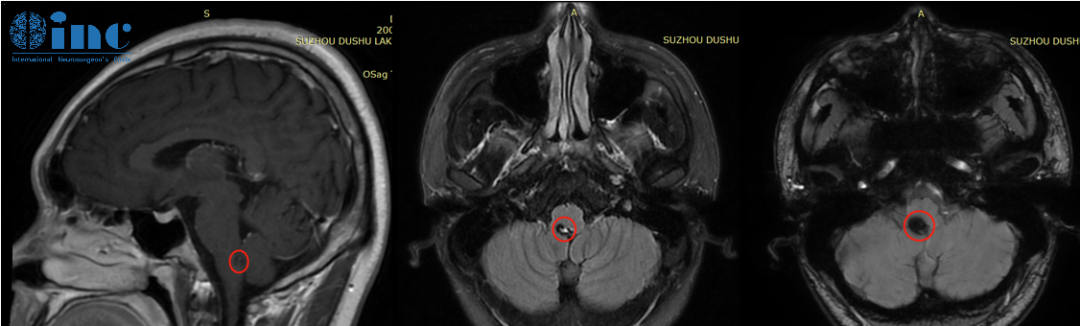

但是却不想竟是“生命中枢”——脑干上出了问题。头部CT显示延髓后方近小脑见大小约6.8*9.9mm的片状高密度阴影,怀疑脑干海绵状血管瘤。

2023年3月26日,安豪和家人来到INC国内合作医院苏州独墅湖医院巴教授咨询办公室,一场和国际脑干手术教授的面对面咨询正在展开……

巴教授:目前来看手术是可行的,但是并不是需的。如果手术的话自己可以替他切除这颗位于脑干-延髓位置的海绵状血管瘤,且由于病灶位于延髓外侧,手术难度并不大,自己有过很多更难的成功手术案例。当然也可以暂时不选择手术进行保守治疗,但是这样就会有大约5%再次出血的概率,脑干反复出血后症状会一次比一次重,造成的神经功能损伤是不可逆的,治疗时机则会直接影响患者预后。